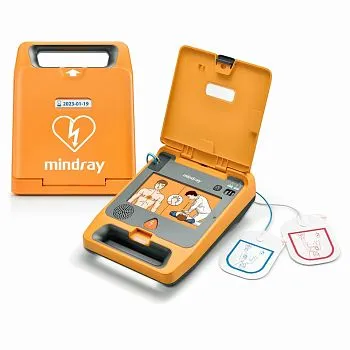

Mindray — это китайская компания, специализирующаяся на производстве медицинского оборудования и решений для здравоохранения. Бренд был основан в 1991 году и за короткое время стал одним из лидеров на мировом и российском рынке медицинской техники.

Mindray предлагает широкий спектр продукции, включая аппараты для УЗИ, наркозно-дыхательное оборудование, мониторы пациента, анализаторы крови и другие медицинские приборы. Компания также разрабатывает программное обеспечение и медицинские информационные системы для облегчения работы врачей и улучшения качества медицинского обслуживания.

Mindray постоянно разрабатывает и внедряет передовые технологии в свои продукты, чтобы совершенствовать качество визуализации и уникализировать своё оборудование. Благодаря высокому качеству продукции и доступным ценам, бренд завоевал доверие клиницистов и пациентов по всему миру.